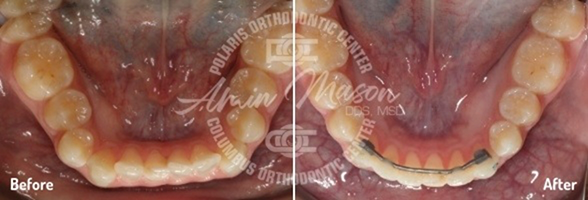

Case 5

This 17-year-old patient came into our office with a multitude of problems we’ve helped many other people fix: teeth crowding, an underbite, and a crossbite of the back teeth (where the upper and lower teeth are offset from left to right). Each of these issues was quite severe, however, and the patient was previously told he needed surgery to correct them all. He said he didn’t want to undergo surgery, so Dr. Mason put together a customized treatment plan. First, he placed a temporary anchorage device (TAD) supported expander to increase the size of the patient's hard palate, and he also used another TAD on the lower teeth to close the spaces. Then, Damon damon self-ligating braces helped move the teeth into their ideal positions. One of the patient’s lower premolars was removed as well. In the end, the patient was able to avoid surgery and achieve excellent results that he could not believe.